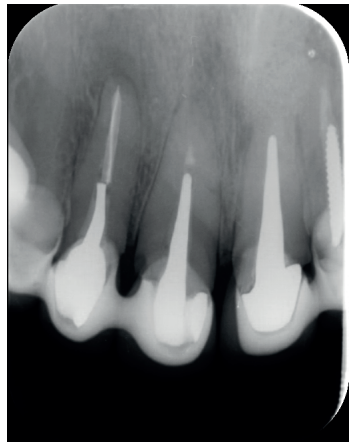

El paciente aporta como estudio radiológico una ortopantomografía (OPG), (Figura 1). Se realizaron radiografías periapicales (Figuras 2 y 3), así como exploración clínica incluyendo la valoración periodontal de los dientes afectados, sin observar profundidades de sondaje aumentadas que pudieran indicar la existencia de lesiones endoperiodontales.